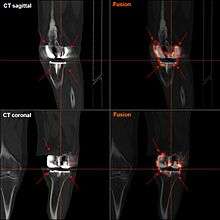

According to a recent review the following tests can be used in the diagnosis of a periprosthetic infection.[11]

- Conventional radiograph: Rule out other conditions such as loosening and/or osteolysis.

- Radionucleotide Imaging: Technetium-99m Sulfur imaging combined with indium-111-labeled leukocytes probably offers improved specificity than either test alone. Gallium 67 scans alone have low sensitivity for infection. FDG-PET imaging has been shown to have variable specificity and sensitivity.

- Serology: Elevated serum C-reactive protein (CRP) and Erythrocyte Sedimentation Rate (ESR) more than three months following arthroplasty are good screening tests.[12]

- Cultures: High sensitivity and specificity, but only if done two weeks following antibiotic discontinuation. Gram stains have low specificity and sensitivity. The predictive value of a positive culture increases if the culture is performed in patient with high clinical suspicion, rather than a screening test.

- Joint fluid leukocyte counts: A joint fluid white blood cell count of more than 500/μl is suggestive of an infection.

- Frozen sections of implant membranes: More than five white blood cells/High power field is indicative of infection.

- Newer tests: Polymerase chain reactions involving the bacterial 16S rRNA have high rates of false positives because they can detect necrotic bacterial debris even in the absence of active infection.[13]

None of the above laboratory tests has 100% sensitivity or specificity for diagnosing infection. Specificity improves when the tests are performed in patients in whom clinical suspicion exists. ESR and CRP remain good 1st line tests for screening (high sensitivity, low specificity). Aspiration of the joint remains the test with the highest specificity for confirming infection.